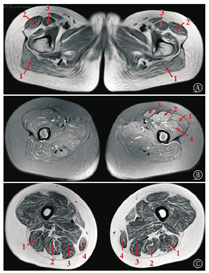

辅助检查:肌酶正常范围;肌电图:双侧腓总运动神经复合肌肉动作电位(CMAP)波幅轻度降低(左侧显著);被检肌肉放松时,见自发电位阳性;轻收缩时,运动单元电位(MUP)形态偏窄或部分偏宽大,伴或不伴多相电位和/或不规则波增多;左侧三角肌及髂腰肌见混合性肌电改变,大部分被检肌重收缩见干扰混合相、混合干扰相或混合单纯相,提示肌源性损害肌电改变,伴轻度神经源性损害改变;心脏B超未见异常;24 h动态心电图:窦性心动过速,偶发室性期前收缩,偶发房性期前收缩;双侧大腿肌肉磁共振成像(MRI)平扫:双侧臀部及大腿肌肉脂肪浸润伴轻度水肿(图1)。患儿妹妹体检与姐姐类似,可见面容略狭长,腭弓高,双上肢远端肌力Ⅴ级,双上肢近端肌力Ⅳ级,双下肢远端肌力Ⅴ级,双下肢近端肌力Ⅳ级,Gower征阳性,肌病步态,神经系统无其他阳性体征。因经济原因,患儿妹妹未行肌电图、MRI等相关检查。